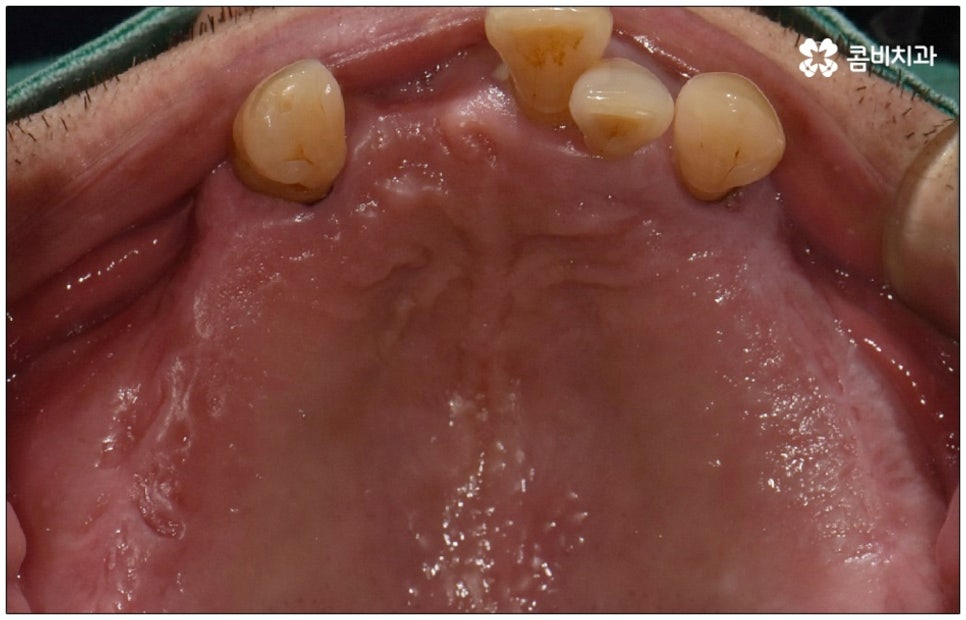

사람의 치아는 영구치에서 유치로 바뀌고 나서는 평생 다시 새롭게 나지 않기 때문에 사고나 구강 질환으로 자연 치아를 상실하게 되면 이를 인공 치아로 대체할 필요가 있어요. 치아 상실에 대해 예전에는 틀니를 많이 이용했지만 관리가 어렵고 탈착식이다보니 음식을 먹을 때 저작 기능이 떨어지며 자칫 탈락하는 경우가 잦아 불편함이 커서 요즘은 임플란트 수술을 통해 인공 치아를 직접 식립하는 쪽을 더 선호하고 있습니다. 임플란트는 잇몸뼈에 인공 치근을 심어 골유착을 유도하는 것이기 때문에 환자분의 잇몸뼈 상황이 식립 성공률과 지속성, 안정성 등에 굉장히 크게 영향을 미치므로 결국 잇몸을 평상시에 얼마나 잘 관리해 주었는지 여부가 중요하다고 할 수 있어요.

성인 이후 치아 상실의 주된 원인은 바로 풍치인데요, 풍치 즉 치주 질환은 잇몸(치은)을 포함한 치아 주위 조직에 급성 또는 만성으로 염증이 생겨서 손상이 일어난 것을 의미하고 있습니다. 이러한 풍치의 주된 원인은 치태와 치석으로, 음식물 찌꺼기와 치아 표면의 세균막(치태=플라그)이 엉겨붙어 굳어진 치석은 평상시의 칫솔질로는 제거되지 않기 때문에 스케일링 치료를 통해 주기적으로 제거해 줄 필요가 있어요. 치석이 점점 쌓이면 세균이 급증하는 온상이 되어 주변 조직에 염증이 발생하기 쉽고 병증이 심해질수록 치주인대와 치조골까지 손상이 깊어져 결국 치아가 빠지게 되는 거예요. 풍치로 치아를 잃게 되면 임플란트를 심는데도 어려움이 있기 때문에 이렇게 상황이 나빠지기 전에 제 때 적합한 치료를 받을 필요가 있어요. 하지만 잇몸의 경우 병증이 많이 깊어질 때까지 잘 알아차리기 힘든 경우가 많으므로 정기 검진 및 스케일링과 같은 평상시의 관리가 중요하다는 말씀을 드린 거예요.

특히 다수의 치아를 상실했을 때 전체적인 교합, 골조직 및 잇몸 상태, 얼굴형과의 조화 등 모든 부분을 종합적으로 고려하여야 하며 노인임플란트 수술의 경우 다양한 변수가 발생할 수 있기 때문에 이러한 고난도 임플란트 케이스에 노련하게 대처할 수 있도록 풍부한 임상 경험과 노하우를 갖춘 의료진인지, 정밀 검진 기계를 보유하고 있는지, 처음부터 끝까지 철저한 케어 시스템을 갖추고 사후 관리까지 꼼꼼하게 진행하는지 등을 잘 살펴보시고 임플란트 수술을 진행할 치과를 신중하게 선택하시길 권유드리고 있습니다.